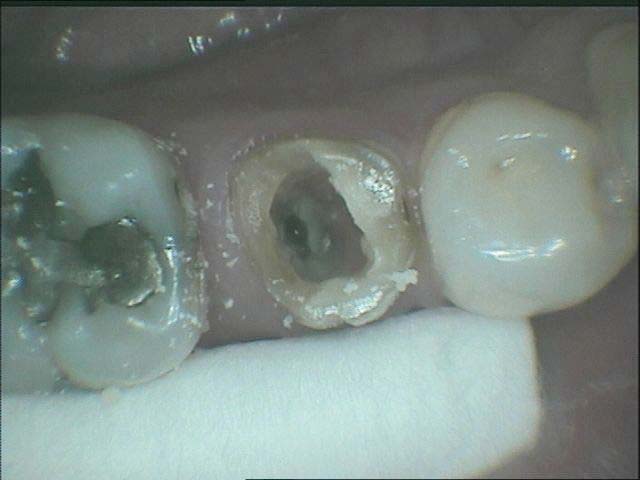

孫先生右下角有一牙齒有嚴重蛀牙,經過診斷後,無法利用此牙根製作假牙,決定採取"即拔即種"的新做法,使用人工植體替代蛀蝕嚴重的牙根,三個月後,孫先生即擁有兼具美觀功能與耐久度的新牙齒了。

斷裂蛀蝕牙根